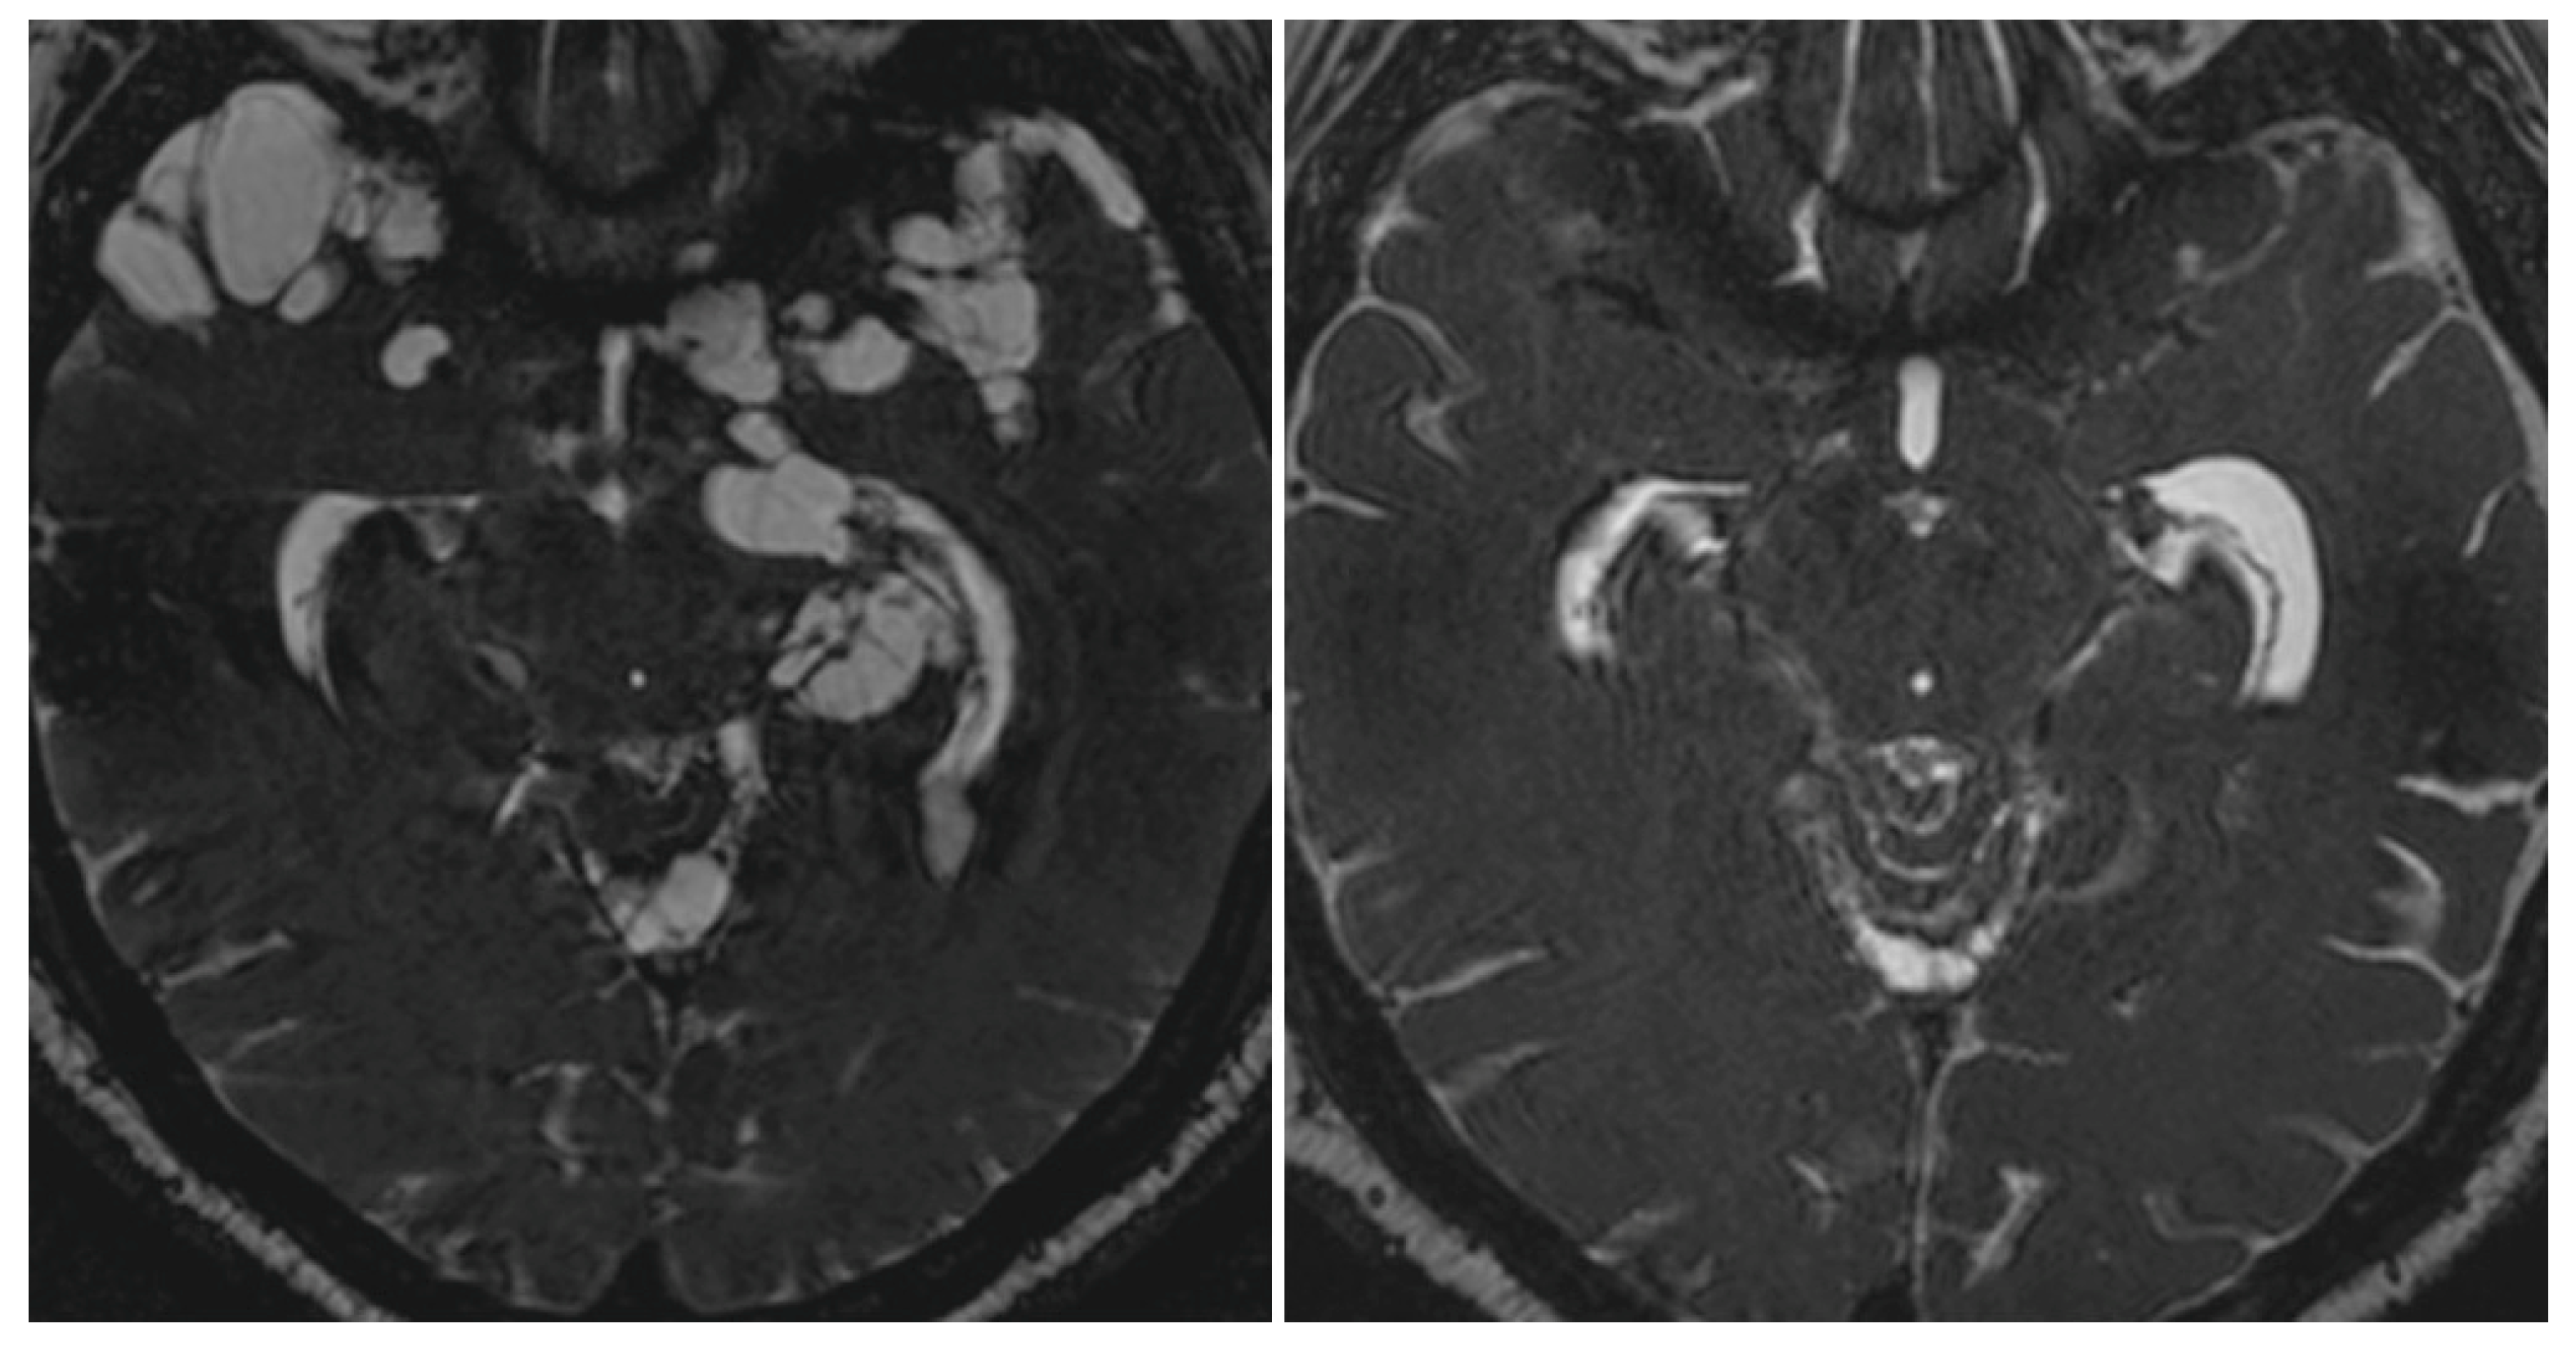

3.1. Neuroimaging Studies